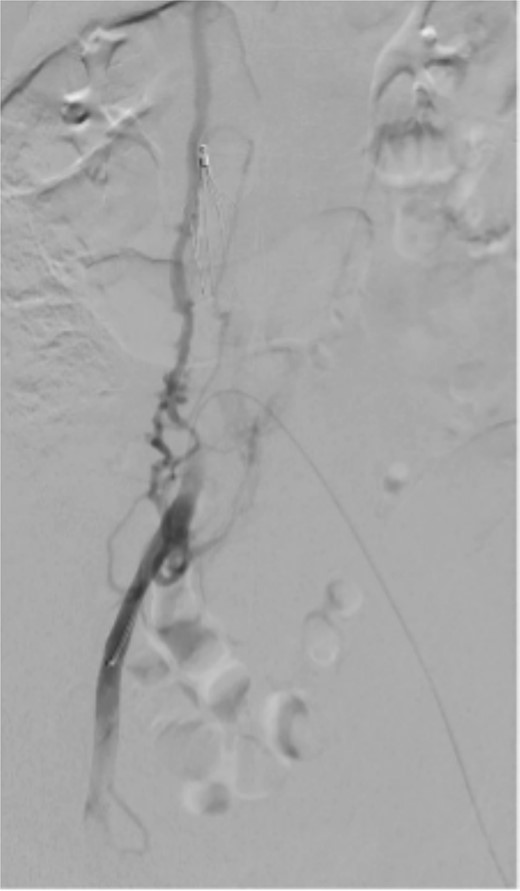

The completion venogram showed smooth contrast flow from the left popliteal vein upwards. The right common iliac vein was stenosed near the confluence, with a large collateral vein as the main outflow into IVC (Fig. 2). As outflow was thought to be adequate, no intervention was done on the right.

Bilateral popliteal venous access was obtained. Venography confirmed patency of the IVC, left iliac vein, and stents. Thrombolysis of the right lower limb was performed with AngioJet Zelante and 10 mg of alteplase (lower dose to minimize hematoma complications). The IVC filter was then removed to allow extension of a Venovo 12 × 80 mm stent positioned in the right iliac vein, and a Venovo 14 × 80 mm superior extension on the left. Both stents were deployed simultaneously in a ‘kissing’ configuration and post-dilatated with Mustang 12 × 100 mm balloons (Fig. 4). The completion venogram showed smooth contrast flow in both limbs with the disappearance of collateral veins.